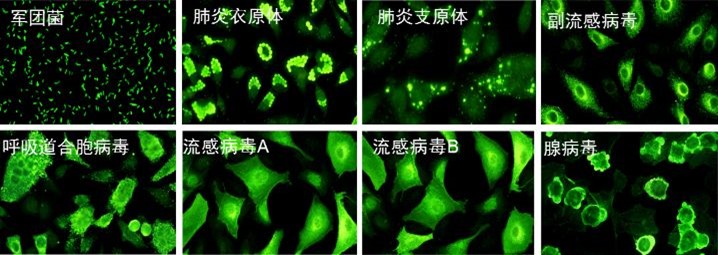

呼吸道抗體譜檢測常見病原體

| 呼吸道病原體譜 呼吸道合胞病毒、腺病毒、流感病毒A型、流感病毒B型、副流感病毒、肺炎支原體、肺炎衣原體、嗜肺軍團菌、抗柯薩奇病毒A型*、柯薩奇病毒B型*及埃可病毒* | IgM | IIFT | |